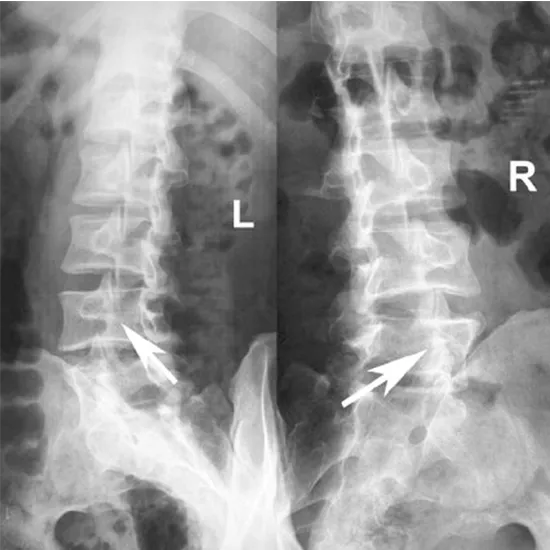

X-ray Lumbar Oblique Views

An X-ray of the lumbar spine is a safe and painless test to visualize the lower back, including the lumbar vertebrae (L1 to L5), intervertebral discs, and surrounding soft tissues, including muscles.